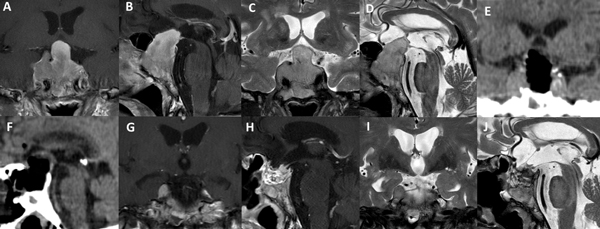

La técnica de “Guante Blanco” se indica en pacientes con macroadenomas no funcionantes, apoplejía pituitaria, enfermedad de Cushing, acromegalia, adenoma secretor de TSH y en portadores de prolactinomas con una clara indicación quirúrgica. La indicación principal es en tumores infradiafragmáticos, es decir, por debajo de la duramadre del diafragma selar o respetando el orificio del anillo dural (Figura 5). Se podría valorar a futuro su indicación en casos con extensión supraselar sin invasión ventricular y sin invasión lateral.

Existen situaciones que contraindican relativamente el uso de esta técnica y precisa un abordaje “extendido”: adenoma en reloj de arena, alto grado de extensión supraselar (e.g. invasión del III ventrículo), extensión para-selar (e.g. englobamiento carotideo), consistencia dura o fibrosa del tumor (Figura 6).

Figura 6. Paciente de 62 años, acromegálica, con adenoma gigante Hardy C y Knosp 4. No fue candidata a abordaje de Guante Blanco. Se utilizó un abordaje extendido para su tratamiento. A-D: RM preoperatoria. E-F: TC del primer día postoperatorio. G-J: RM postoperatoria.